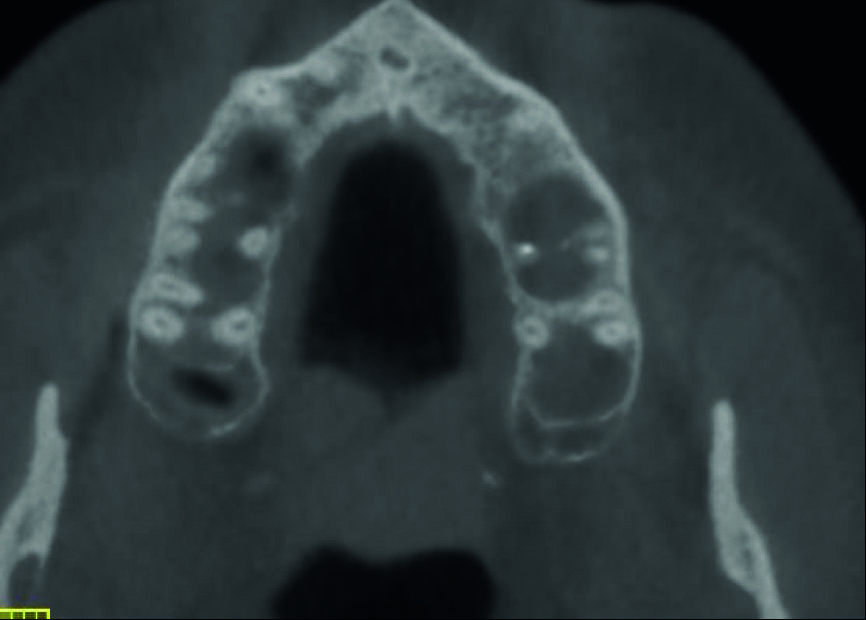

Un patient avait été adressé au cabinet en raison de problèmes associés à la fracture d’une lime. Il était pilote de ligne et se plaignait d’écoulements nasaux purulents lorsqu’il était en vol. La radiographie pré-opératoire (Fig. 1) a distinctement montré la présence de deux fragments d’une lime fracturée dans les canaux mésiaux et d’un cône traversant l’apex de la racine palatine. Après l’imagerie CBCT avec iCAT, il est apparu clairement que le sinus gauche était presque totalement rempli de liquide inflammatoire (Fig. 2) et que le cône présent dans le canal palatin pénétrait dans le sinus. Sur l’image de reconstruction multi planaire (MPR), nous pouvions également distinguer les deux fragments de lime fracturée dans les deux canaux mésiaux (Figs. 3 et 4) et aussi un autre fragment dans le sinus sans aucun contact avec le canal (Fig. 5). L’utilisation de différents filtres nous a permis de visualiser les fragments de lime (Figs. 6–9), ainsi que l’inflammation et le fragment de lime fracturée à l’intérieur du sinus. Nous avons également mieux perçu la position du cône qui émergeait du canal palatin et pénétrait dans le sinus.